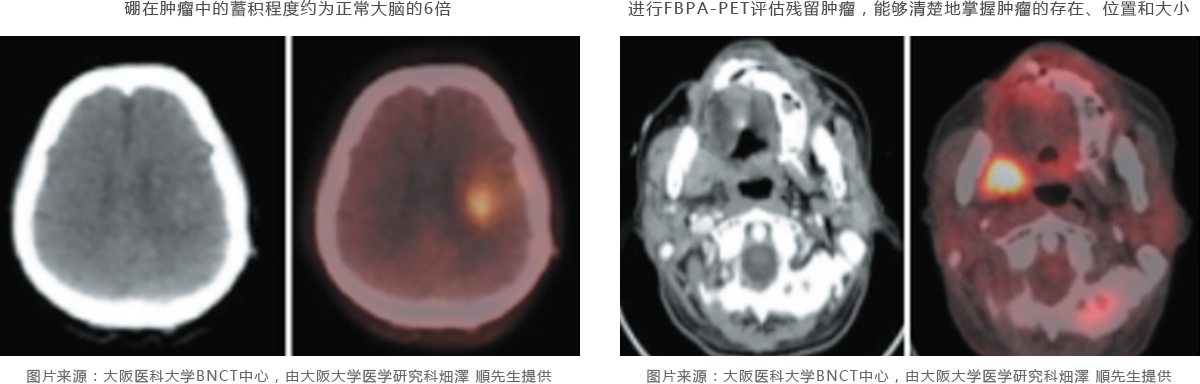

BNCT的有效性主要取決于硼濃度及其在靶腫瘤細胞中的分布,也就是讓更多的硼有效地積累在癌組織而不是周圍的正常組織中,硼苯丙氨酸(BPA)是目前常用于BNCT的含硼藥物,但集聚程度因腫瘤而異,因此在中子照射前有必要對腫瘤處的硼化合物集聚程度進行預(yù)測,硼藥物在癌細胞中的蓄積程度可以通過稱為FBPA-PET的核醫(yī)學(xué)試驗預(yù)先確定,通過PET檢查將其全身分布情況圖像化,從而推測硼化合物的集聚程度和治療效果。同時,在治療癌癥時,區(qū)分癌癥和一般炎癥也很重要。FBPA藥物不容易聚集在炎癥區(qū)域,在區(qū)分癌癥和炎癥方面也非常出色,未來,F(xiàn)BPA-PET檢測將在擴大BNCT治療的癌癥數(shù)量中起重要作用。